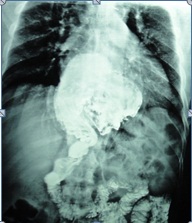

شهد مجمع سفير الحسين(ع) الطبي التخصصي إجراء أول عملية من نوعها في المحافظة لتصغير جدار المعدة بالناظور بحسب مدير المجمع

وقال الدكتور عبد الجبار كاظم لوكالة نون الخبرية "أن العملية أجريت لمريض يعاني من السمنة المفرطة فقد كان وزنه (220كغم )حيث تمت عملية تصغير جدار المعدة وربطها بالأمعاء بواسطة الناظورمن قبل فريق جراحي متخصص مؤلف من الدكتور بازكي ( إيراني الجنسية) والدكتور صباح كريم الحسيني (اختصاص جراحة عامة)والدكتور عبد الرزاق خلف (جراحة عامة) والدكتور جابر محسن( اختصاص تخدير)، مشيرا إلى أن العملية استغرقت ثلاث ساعات مؤكداً على أن العملية تكللت بالنجاح التام وبعد عدة أشهر من الاستمرار بمتابعة حالة المريض الصحية أصبح وزنه في الوقت الحاضر(100كغم) .